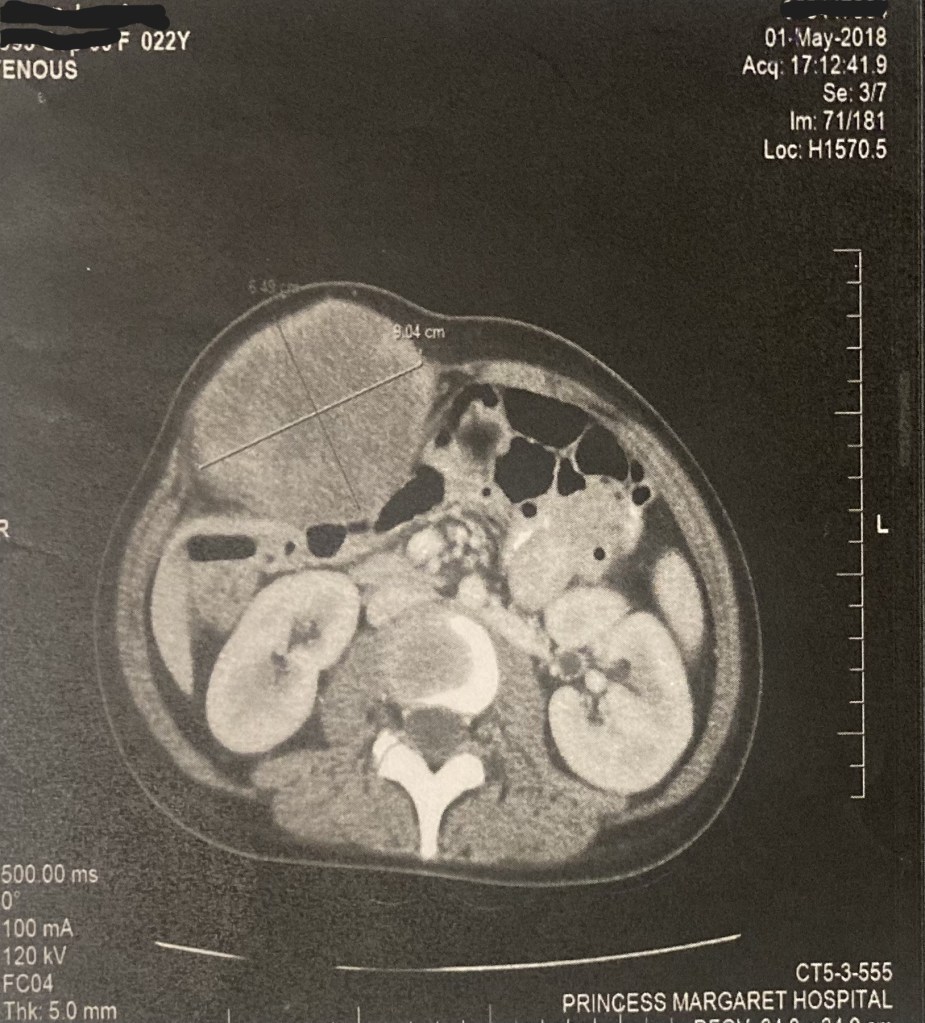

The scan was sort of absurdly funny. He booked me a scan at RVH, because he could just call and tell me yay or nay, no need to drive down to Toronto for a MRI. But the technologist, who didn’t know what the tumor is because few people do, just told my surgeon there was nothing on the scan, and he had to call and yell at them to send him the images so he could see. It took them a month to send him the images, literally on a DVD in the mail instead of an email for some nonsensical reason.

It was a Desmoid.

He referred to me a Desmoid specialist right away, and it took less than a month to see her. But in the two months since I had first noticed the golf ball, it had doubled in size to a baseball or grapefruit. I stopped wearing the form fitting clothes I loved and hid inside baggy sweaters. I was a health nut like my dad and proud of my six-pack abs, even after the two surgeries, but it was too embarrassing. She told me that she couldn’t operate on it. She referred me again to a sarcoma specialist who could order chemo.

The specialist told me most Desmoids are indolent and that she wanted to watch it. I told her it had doubled in size within two months. She doubted me and ordered another MRI and a biopsy. When it came back, it confirmed I was right.

The tumor kept getting bigger for six months. People started asking me if I was pregnant, that’s how big it was. I went back to my maternity clothes. I felt damned- I had traded in my son for this demonic cancer baby thing. I also felt more sure that I had made the right choice to give him up. I would be going through chemo while trying to raise a toddler. Despite my parents thinking I’d have an easier time, I had a worse time. Who knows what life would have been like for Vincent?